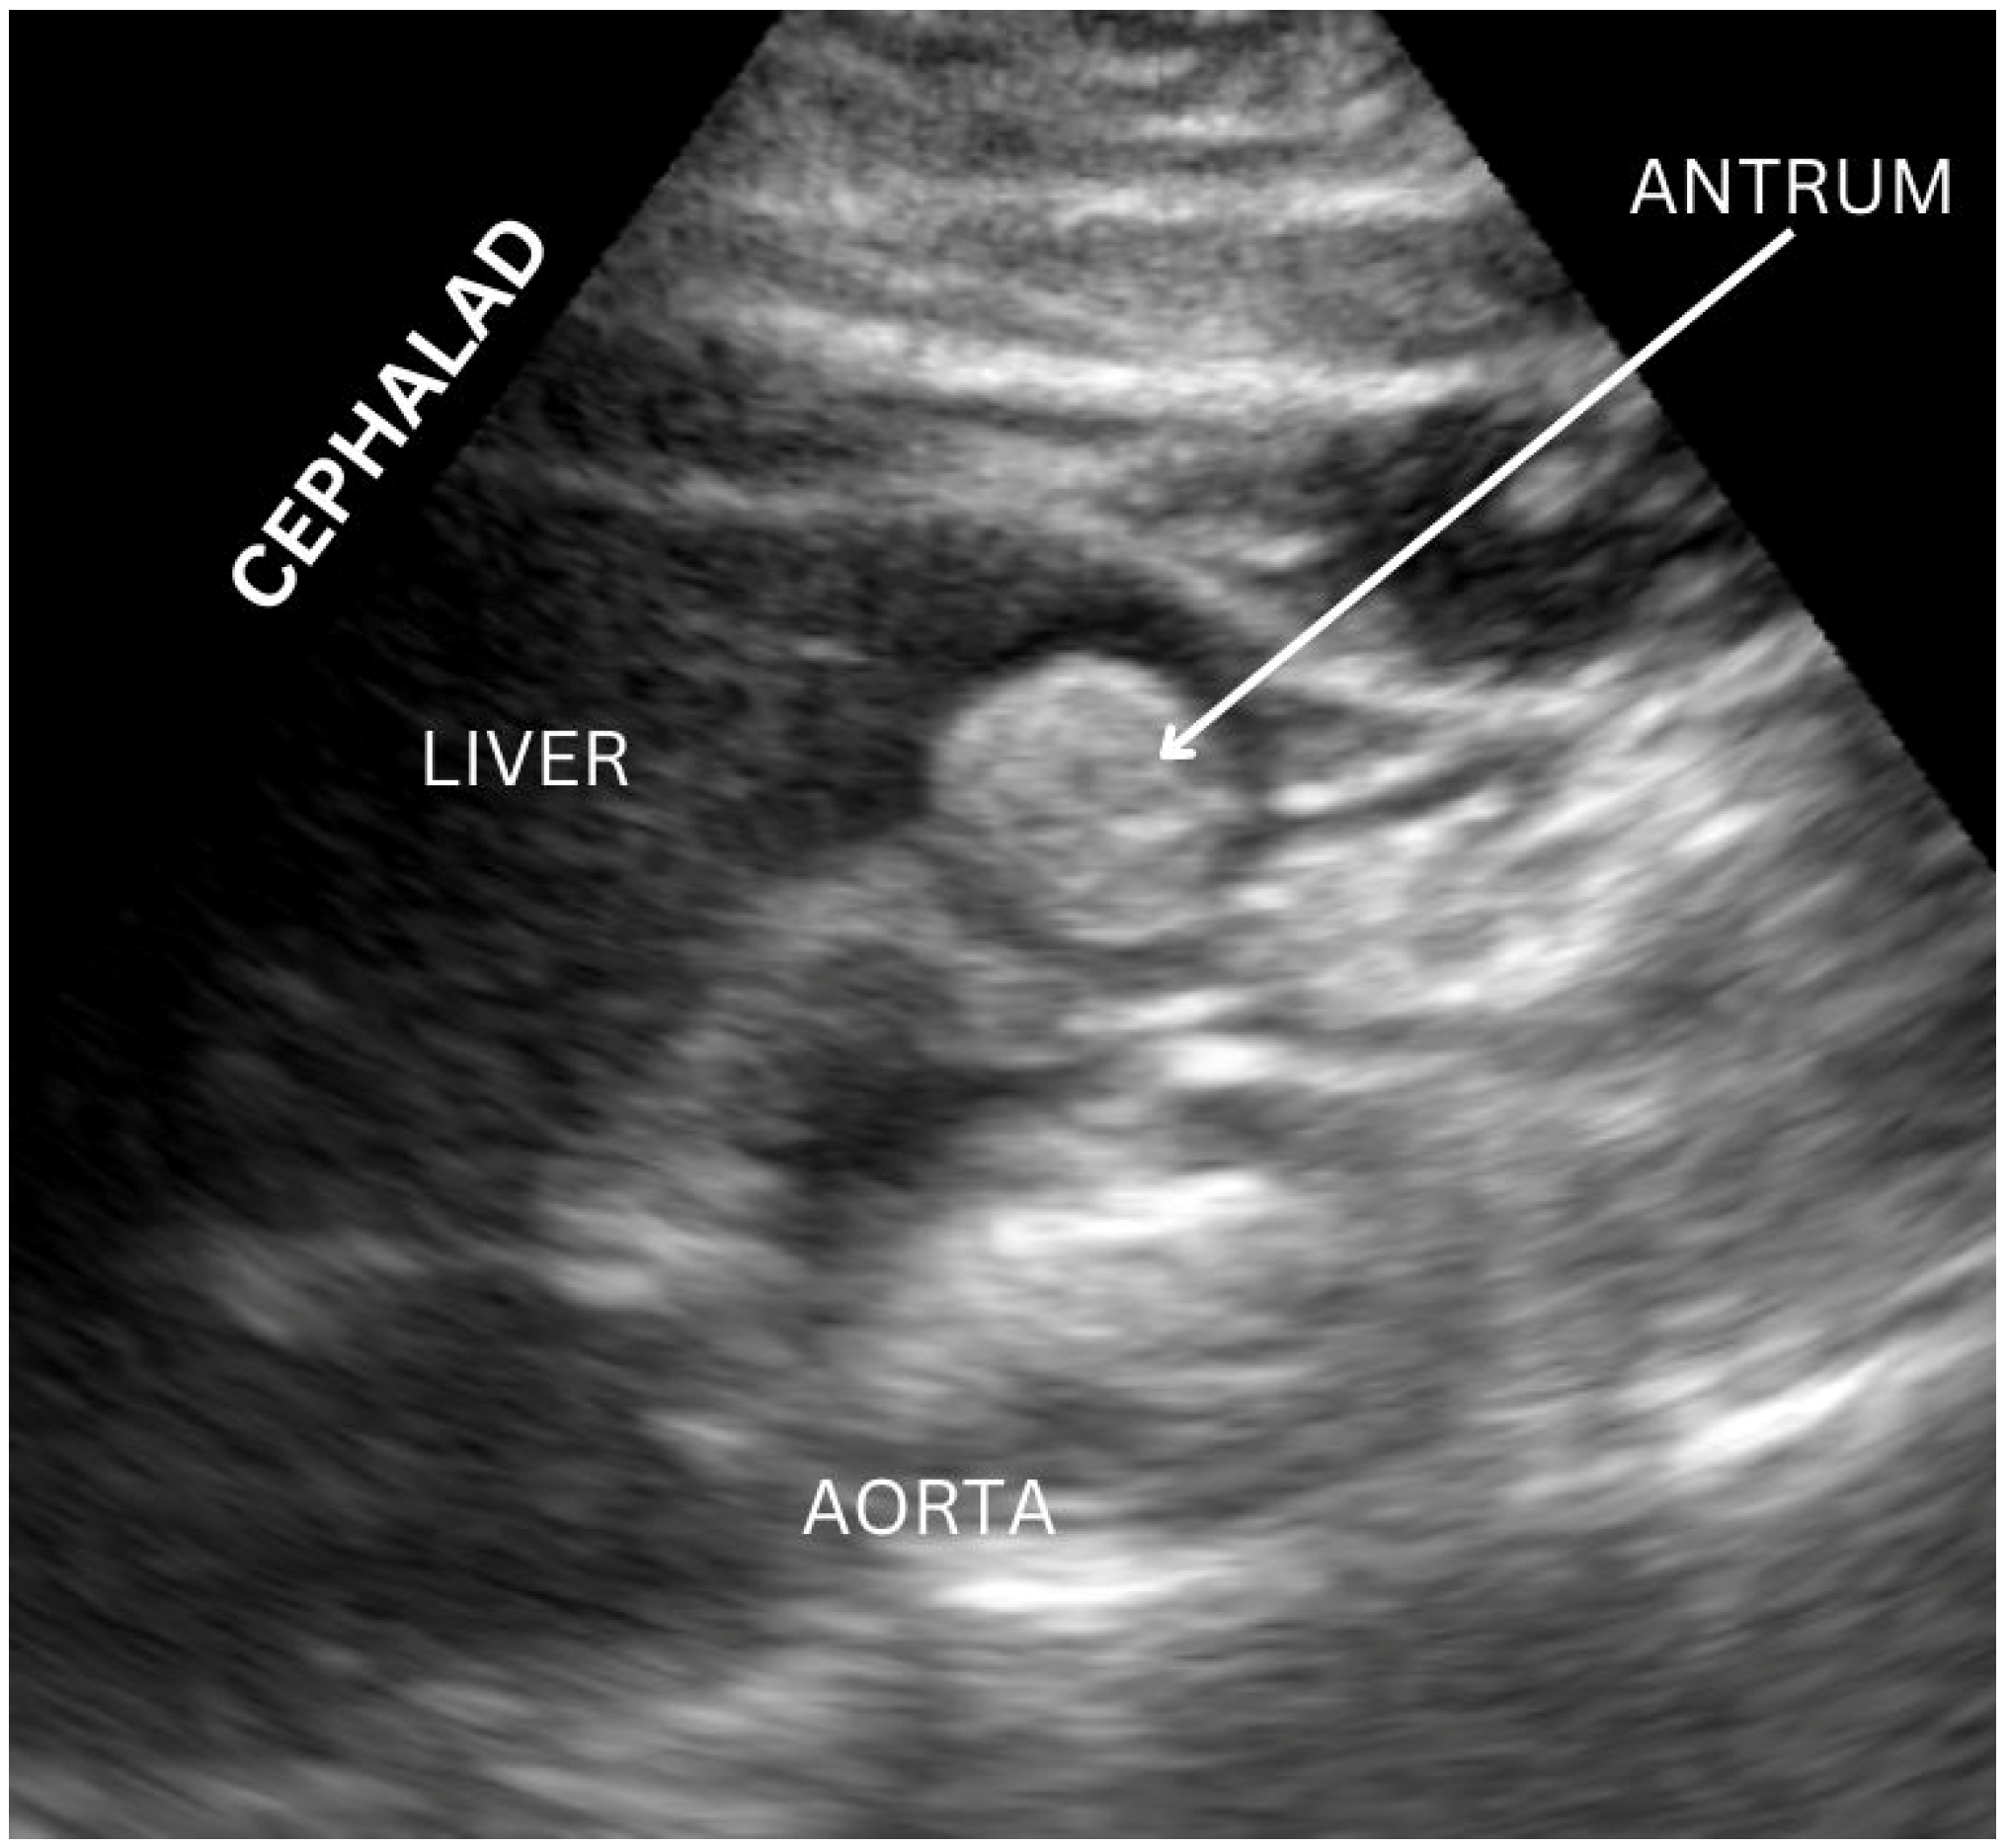

Figure 2.

Example of gastric ultrasound image acquisition with gastric antrum visualized. Image originally acquired by authors.

Once an appropriate patient has been identified, a standardized approach to performing gastric ultrasound can be followed, first with the patient in a supine position and then in the right lateral decubitus position (Figure 1). A curvilinear low-frequency probe is frequently used for adult patients, while a high-frequency probe may be more appropriate for pediatric patients [12]. The antrum has a reliable location, and, particularly in the right lateral decubitus position, it also has a more dependent location for gastric contents to gather while air is displaced laterally away from the sonographic beam [17]. The transducer is optimally placed in the midline under the xiphoid; at this location, the antrum is identified inferior to the left hepatic lobe and anterior to the retroperitoneal pancreas (Figure 2). An optimal view includes the abdominal aorta and superior mesenteric vessels which are distal to the antrum [18]. When empty, the antrum has been described as an ovoid shape with the anterior and posterior stomach walls in close proximity to one another; however, after ingestion of fluid, the antrum becomes distended with hypoechoic content, while after ingestion of solid food, the antrum may demonstrate a “frosted glass” appearance as artifacts from the interface between mucosa and air preclude the sonography of posterior structures [12,17,18].